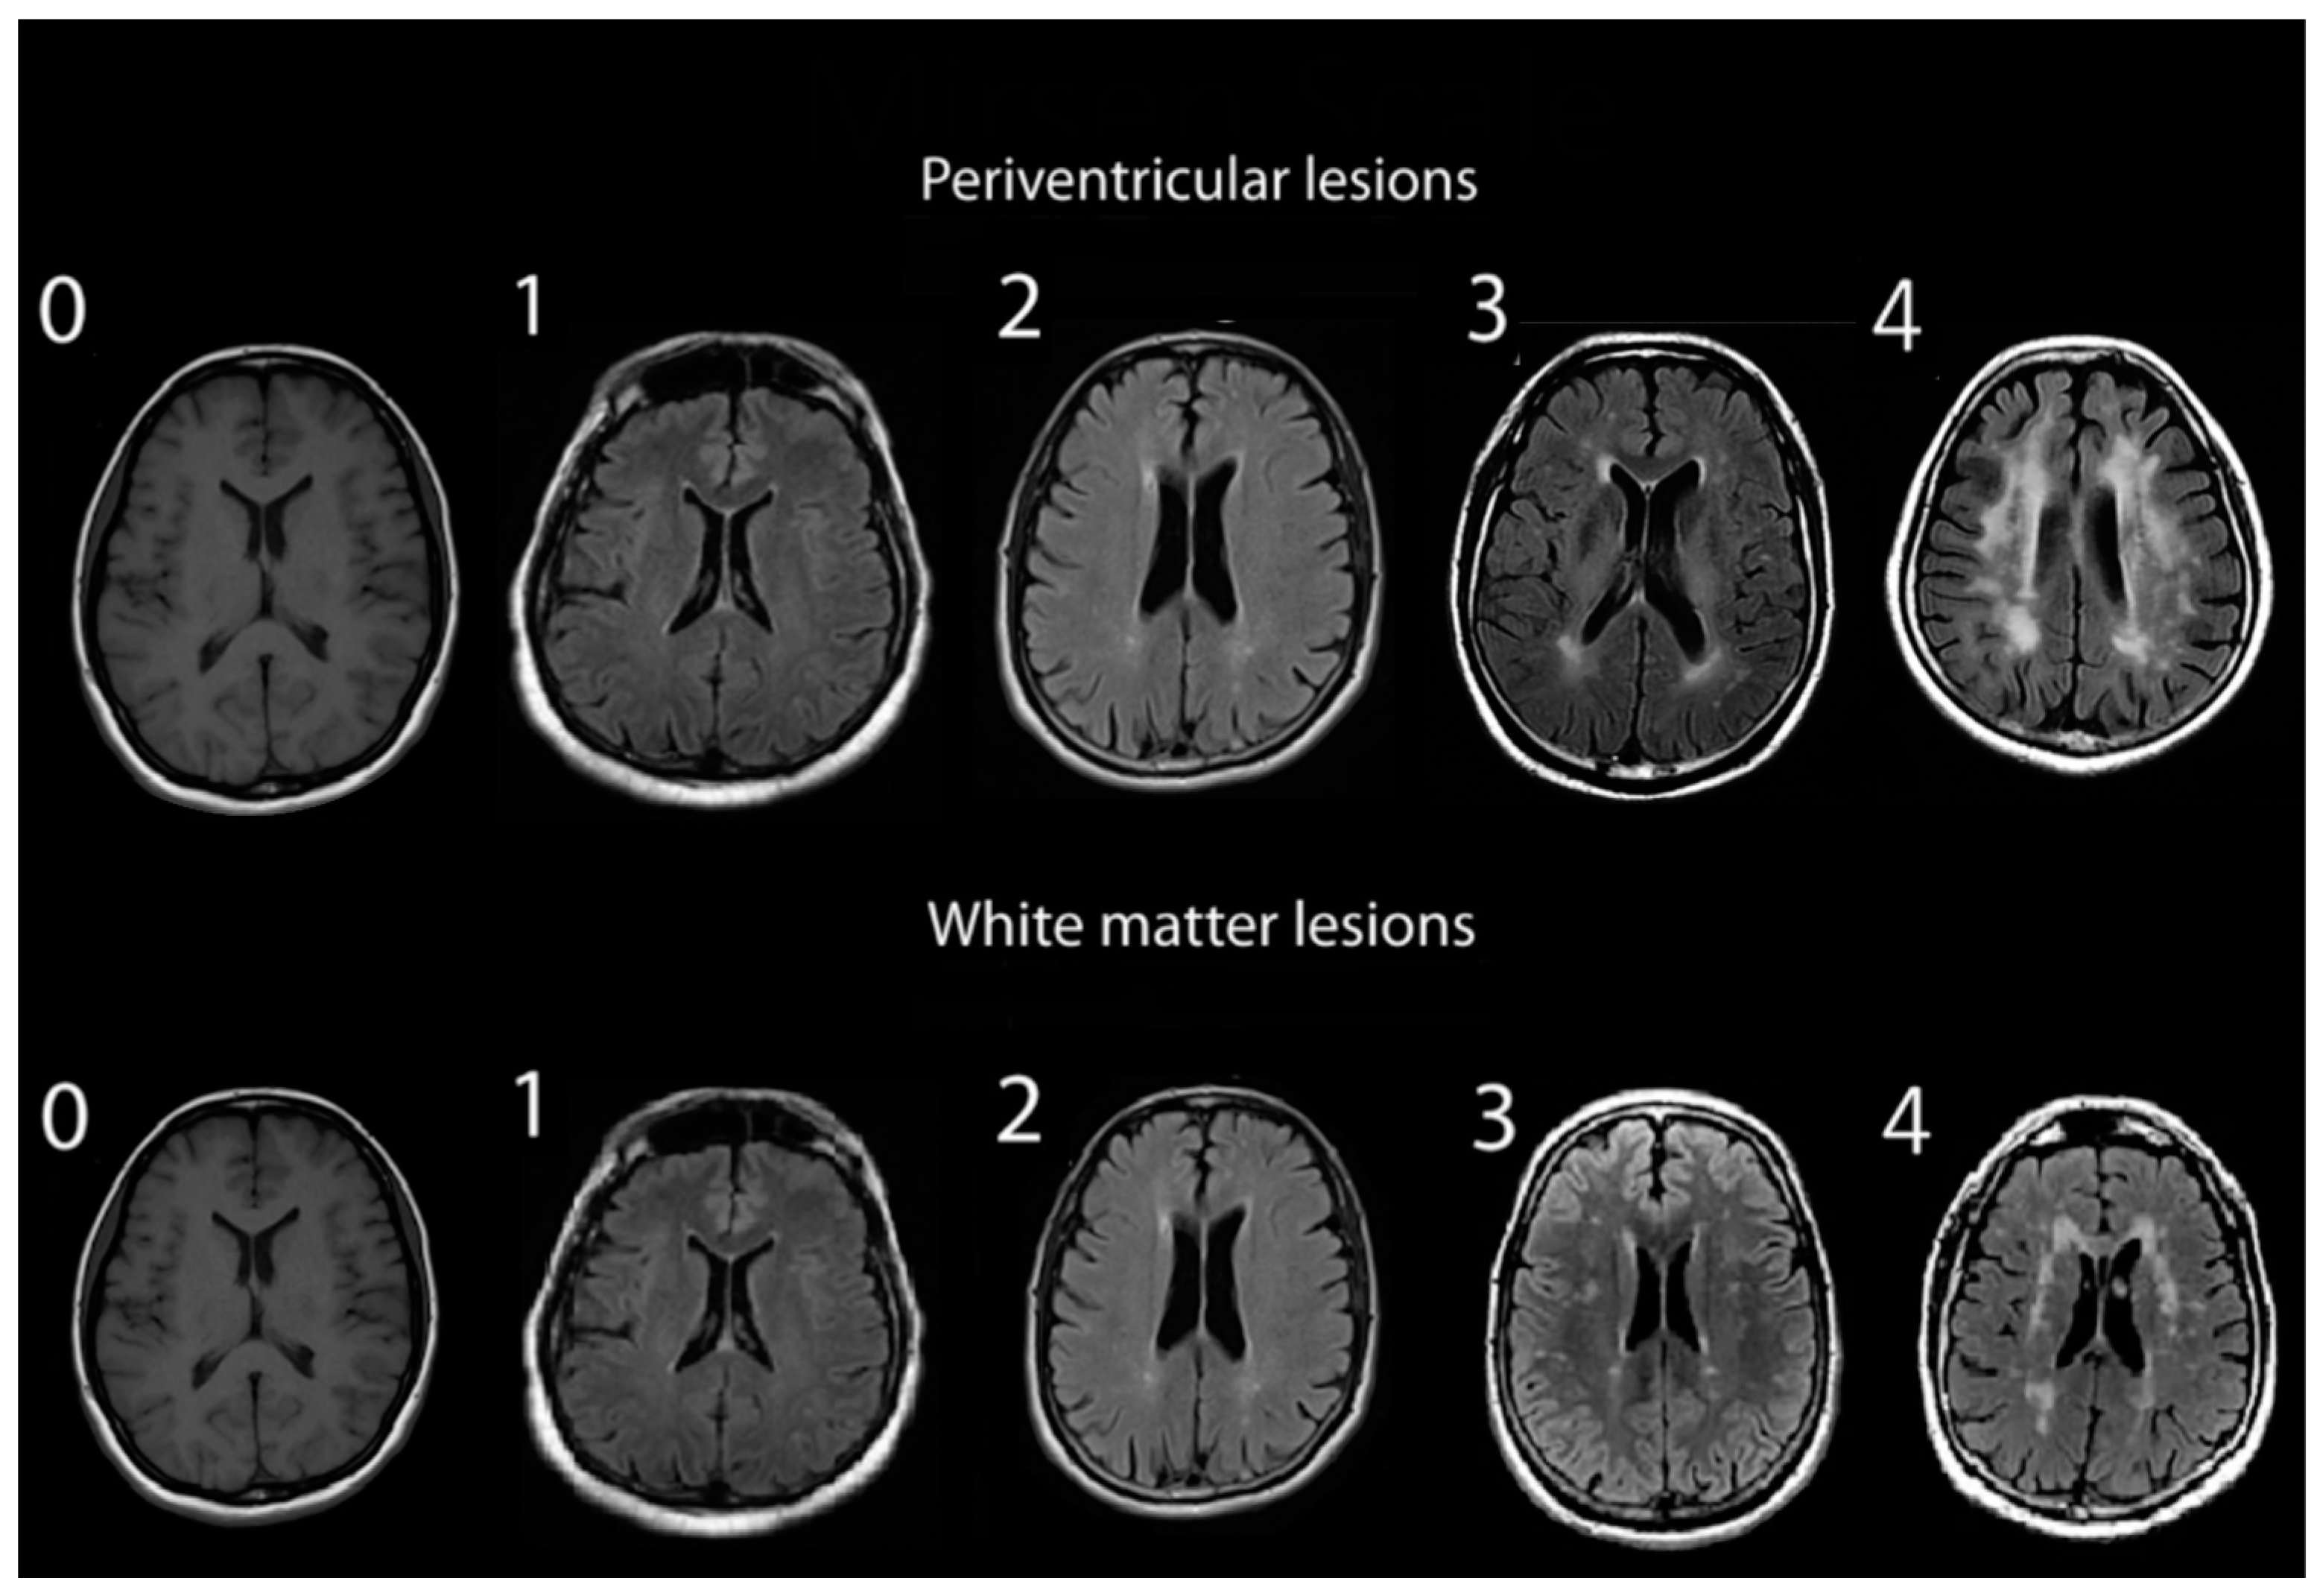

2.2. Assessment of White Matter Hyperintensities

- Mäntylä, R.; Erkinjuntti, T.; Salonen, O.; Aronen, H.J.; Peltonen, T.; Pohjasvaara, T.; Standertskjöld-Nordenstam, C.G. Variable agreement between visual rating scales for white matter hyperintensities on MRI. Comparison of 13 rating scales in a poststroke cohort. Stroke 1997, 28, 1614–1623. [Google Scholar] [CrossRef]

- Fazekas, F.; Chawluk, J.B.; Alavi, A.; Hurtig, H.I.; Zimmerman, R.A. MR signal abnormalities at 1.5 T in Alzheimer’s dementia and normal aging. AJR Am. J. Roentgenol. 1987, 149, 351–356. [Google Scholar] [CrossRef]

- Mirsen, T.R.; Lee, D.H.; Wong, C.J.; Diaz, J.F.; Fox, A.J.; Hachinski, V.C.; Merskey, H. Clinical correlates of white-matter changes on magnetic resonance imaging scans of the brain. Arch. Neurol. 1991, 48, 1015–1021. [Google Scholar] [CrossRef]